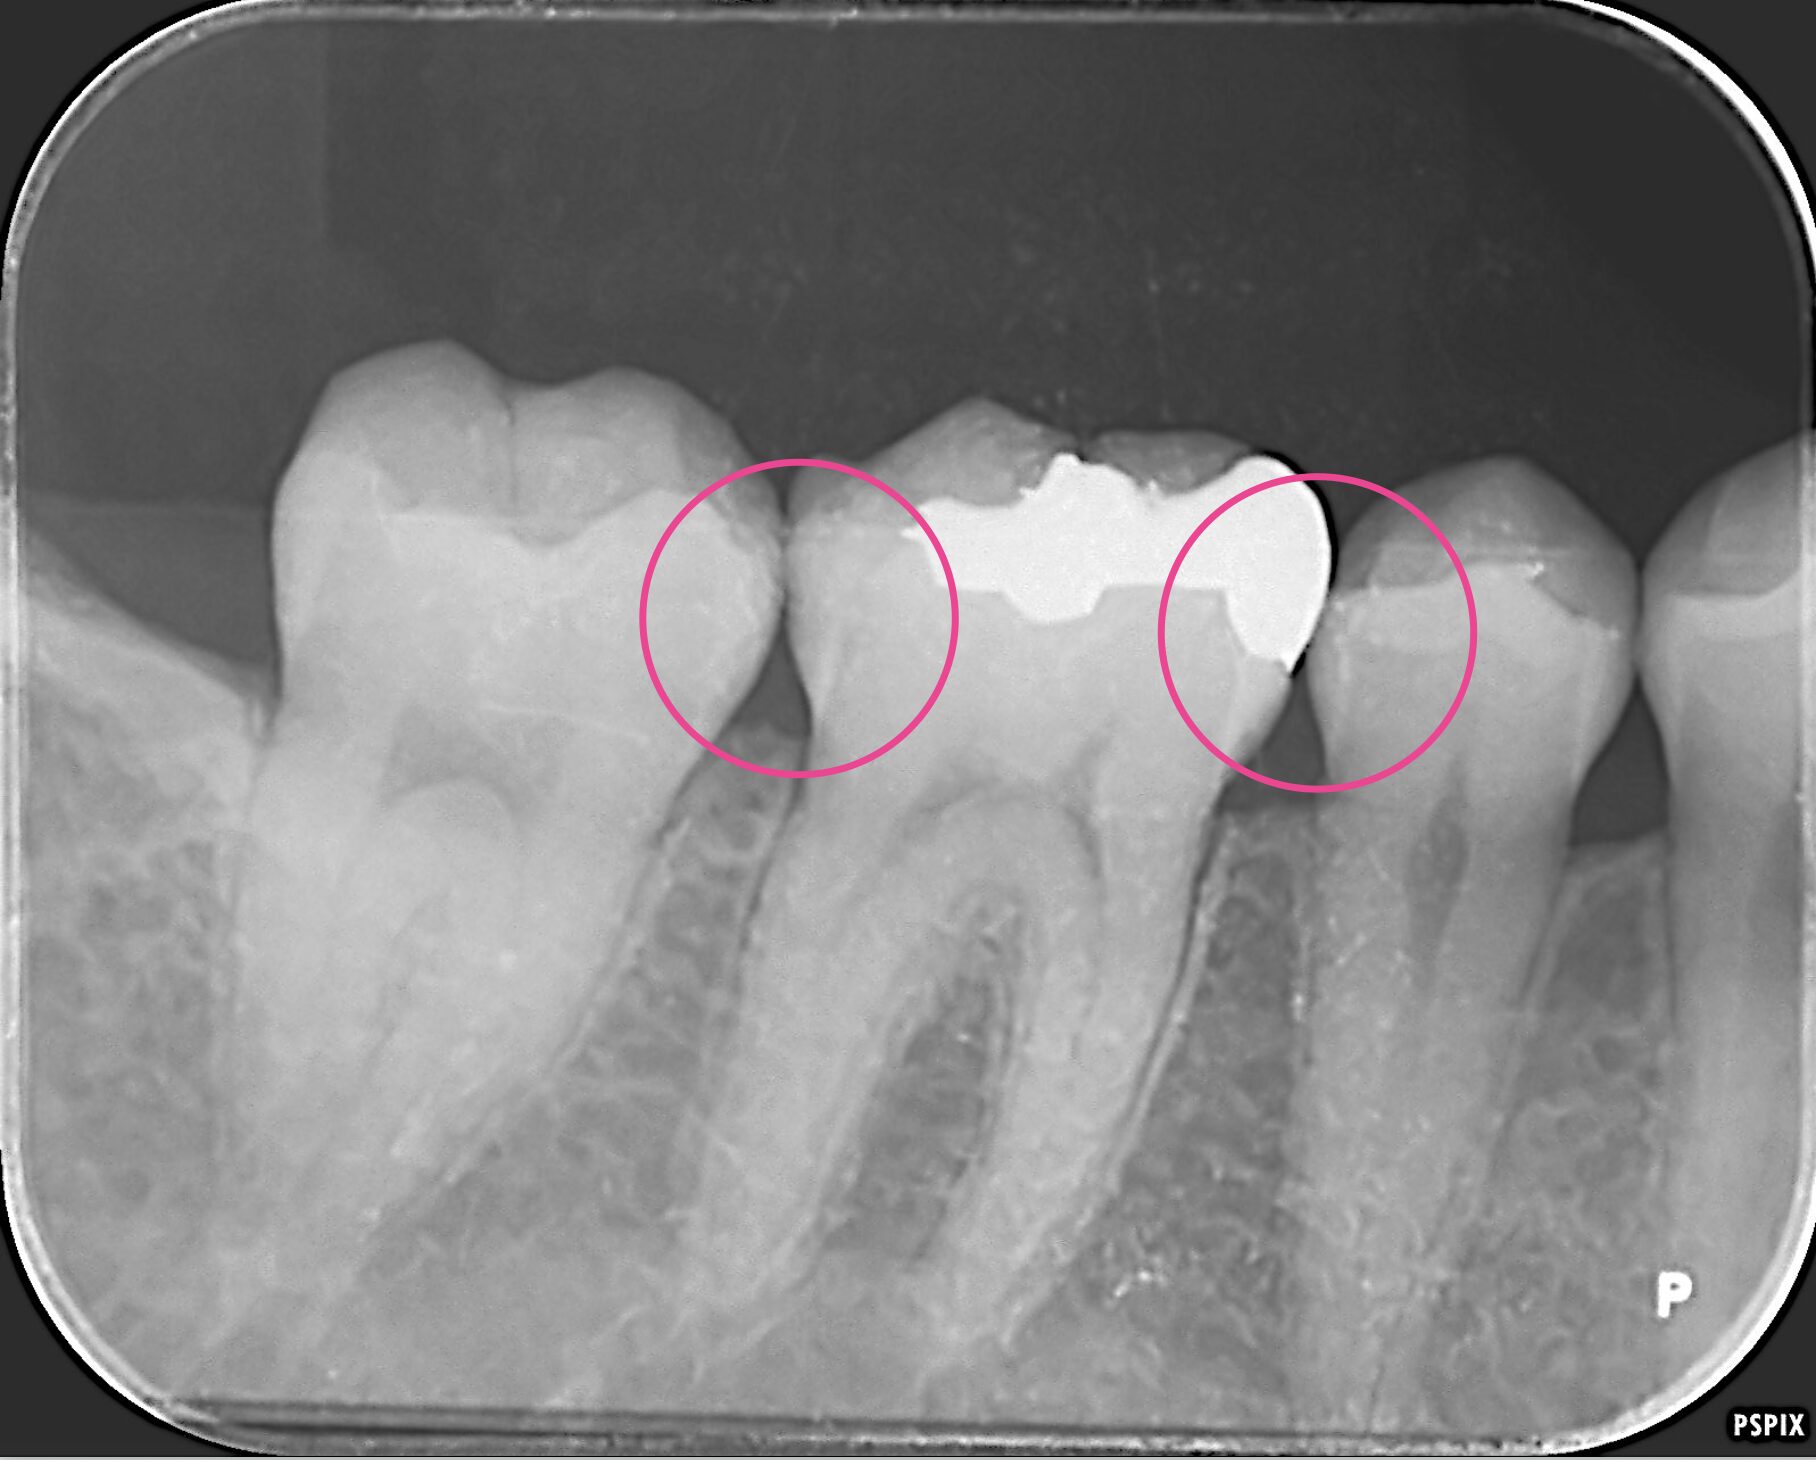

レントゲン写真

銀歯のある歯の前後の歯にも虫歯があります。 -